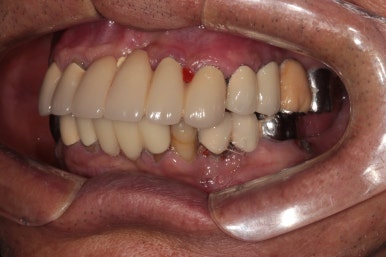

정면에서 찍은 구강 내 사진입니다.

대부분의 치아가 크라운으로 씌워져 있으셨어요. 아무래도 보철물이 너무 많다보니, 구강위생관리가 쉽지 않으신 상태였습니다.

최대한 가성비 있는 치료를 원하셨고, 살릴 수 있는 치아 및 크라운은 남겨두고 싶어 하셨어요.

측면 사진입니다.

먼저 왼쪽 사진이 환자분의 우측 사진인데요, 아래턱 어금니 부위는 이미 치아가 없어진지 오래되어 깔끔하게 나은 잇몸상태를 볼 수 있었습니다.

위쪽은 치석이 너무 많았습니다. 만성 치주염이 심하신 상태였죠..

오른쪽 사진이 환자분의 좌측 사진입니다. 여기서 잘 안보이실 수 있지만, 왼쪽 아래 송곳니 부위에 잇몸 속 고름이 잔뜩 차서.. 흔들흔들한 상태였어요.